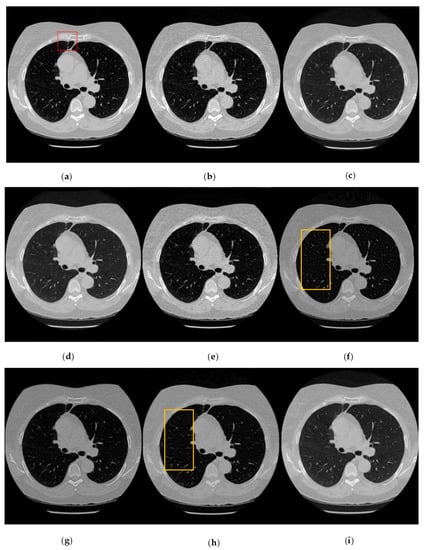

3.5. Results and Analysis